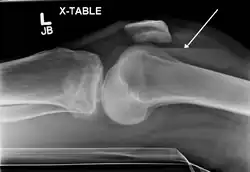

Lipohemarthrosis (presence of fat and blood from bone marrow in the joint space after an intraarticular fracture) seen on X-ray in a person with a subtle tibial plateau fracture -

Lipohemarthrosis due to a tibial plateau fracture -

A tibial plateau fracture seen on X-ray